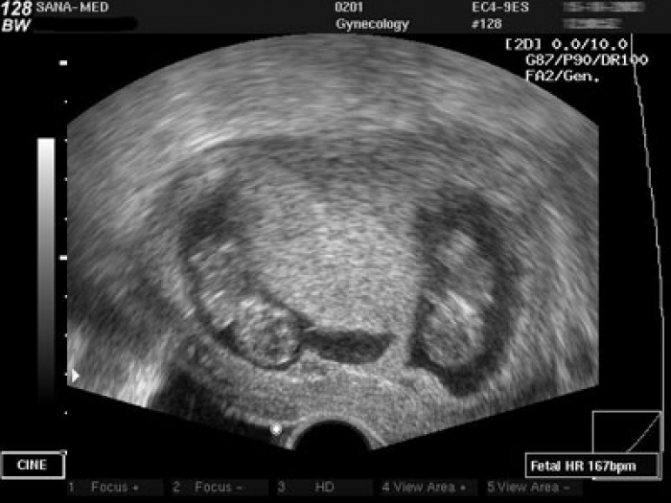

Как выглядит двойня на ранних сроках? Поначалу врач видит только два темных пятнышка. Кроме того, отчетливо прослушивается биение двух сердец, видны две плаценты и два амниотических пузыря. На фото можно увидеть снимок УЗИ близнецов.

На ранних сроках при проведении УЗИ оцениваются следующие параметры плода:

- копчико-теменной размер — КТР, близнецы обычно имеют меньшие размеры, чем одиночные эмбрионы, и к 12 неделе достигают роста 6 см и массы тела 8 г;

- бипариетальный размер — БПР, расстояние между височными костями черепа;

- частота сердечных сокращений — 110-150 уд/мин;

- сформированность нервной трубки;

- наличие носовой косточки;

- толщина воротникового пространства — его расширение вместе с уменьшением носовой косточки указывает на синдром Дауна;

- сформированность внутренних органов.

Нередко на снимке УЗИ заметно, что один эмбрион меньше другого. Если расхождение невелико и составляет всего лишь несколько миллиметров, то беспокоиться не нужно, размеры выровняются или в процессе беременности, или после рождения малышей.